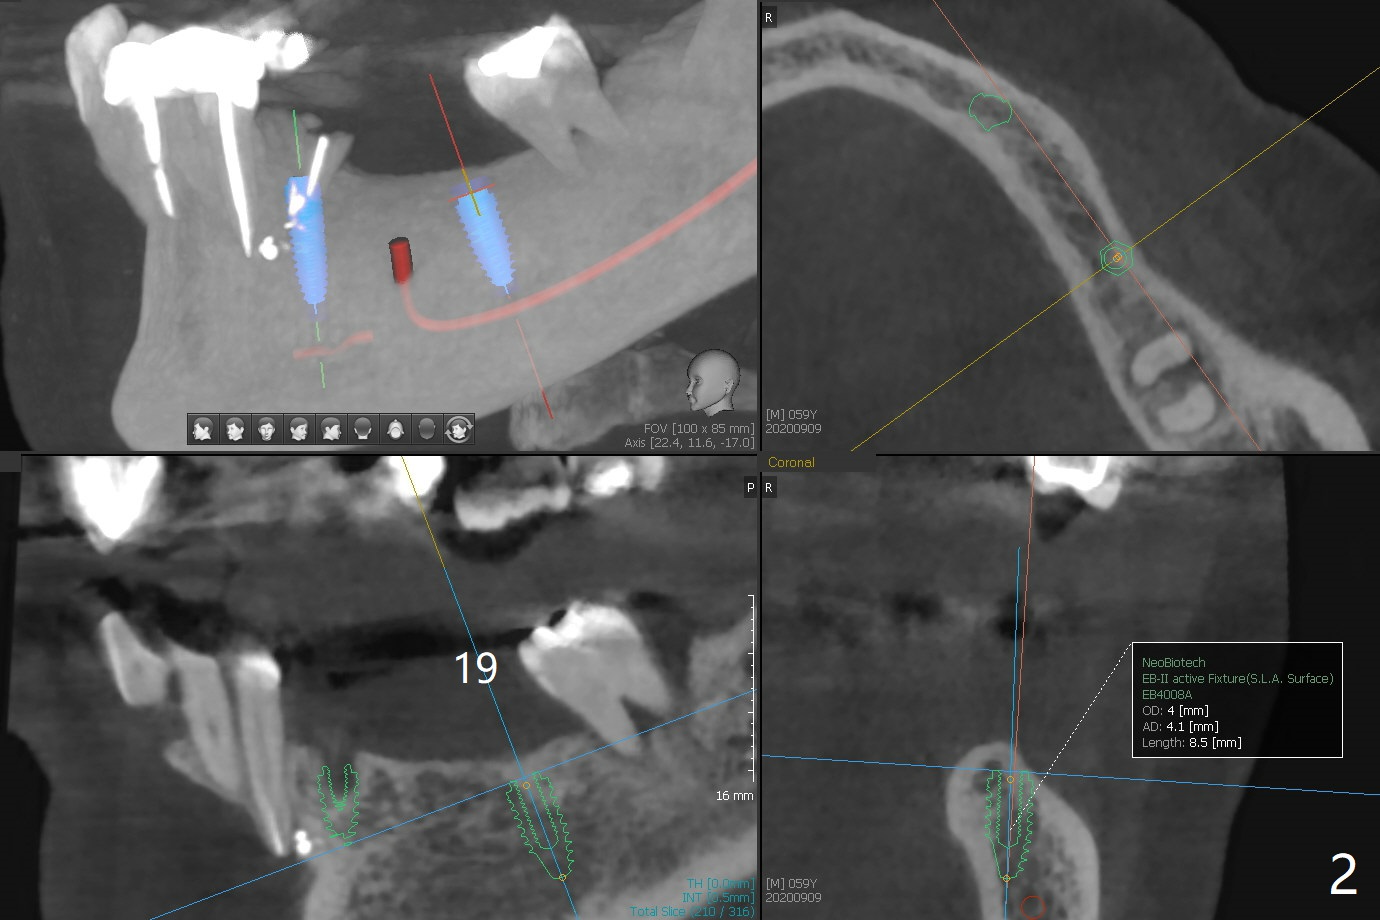

A 59-year-old woman has an abscess buccal to #21 (residual root), immediate placement being imminent, while the teeth #19 and 20 have been missing for a while. Since the ridge is narrow even at #21, three narrow implants will be placed at these sites (Fig.1-3). Please place an implant as close to the lingual (L) plate (but not to touch it to avoid deviation during placement) at #21 (Fig.1).